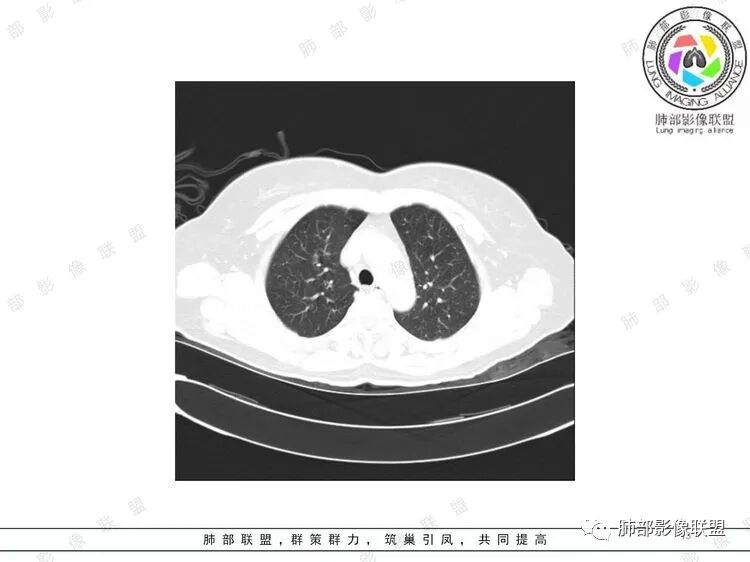

胸CT:双中下肺支气管壁明显增厚,双下肺胸膜下可见实变区。部分病变呈楔形影。

老年女性,咳嗽咳痰低热20天,双肺野散在结节影,随机分布,双肺下叶支气管血管束增粗,支气管管腔狭窄,胸膜下结节斑片影,临床有血尿,痰培养白念阳性,低氧血症。血管炎抗体阴性。从影像看主要侵犯的是血管,血管壁增厚,血管炎抗体阴性不大支持,患者有血尿,考虑膀胱肿瘤引起转移,但是膀胱彩超没发现占位,估计血尿是膀胱炎引起。从影像看考虑侵袭性曲霉菌病?血管炎?实在没有思路。

双肺支气管管壁弥漫性增厚,管腔狭窄,下叶为主,伴多发高密度结节影,边缘模糊,双肺支气管血管束明显增粗,临床症状咳嗽低热,有血尿,首先考虑血管炎

支气管壁增厚,两下肺为主,沿支气管血管束分布斑片状、结节状病变,中轴间质增厚。疾病谱可能有:1.气道来源疾病:结核、曲霉、支原体等;2.间质来源疾病:血管、淋巴系统。结合有血尿,使用激素后尿色变淡、抗生素治疗效果差等病史,考虑血管炎可能性大。

影像上:多发结节沿血管分布;双下叶支气管血管束简直增厚,偏血管,支气管通畅

因为支气管壁增厚,远端应该小气道病变,这个不是,反而是血管增粗明显

加上结节的分布,支持血管相关病变